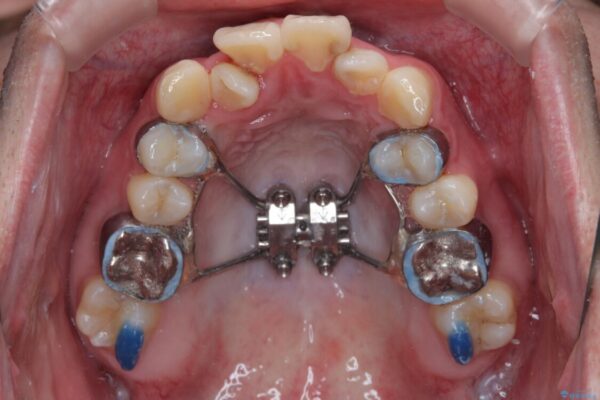

治療方針

このような歯列の狭さに起因するデコボコを改善するために、**MARPE(骨に固定する上顎急速拡大装置)**を使用して、上顎の横幅を拡大し、これにより歯が並ぶためのスペースを確保し、メタルブラケットを用いて歯列を整えていく計画としました。

治療途中

• 1年でここまで変わる!歯列のがたつきと正中のズレを改善した矯正治療(メタルブラケット×MARPE) 治療途中画像